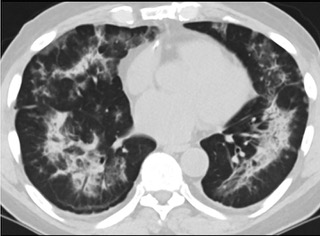

疑點(diǎn)一,電子煙患者的CT影像和臨床表現(xiàn)并不具有特異性。所謂美國(guó)電子肺炎患者,其實(shí)是對(duì)沒(méi)有其他合理診斷證據(jù)、吸食電子煙肺炎患者的統(tǒng)稱。這些患者在病發(fā)前90天內(nèi)吸食了電子煙,尤其值得注意的是,部分患者的CT影像特征和臨床表現(xiàn)與病毒性肺炎患者極其相似。

中、下肺軸位CT平掃顯示毛玻璃樣混濁伴胸膜下保留。(同一病人CT影像)